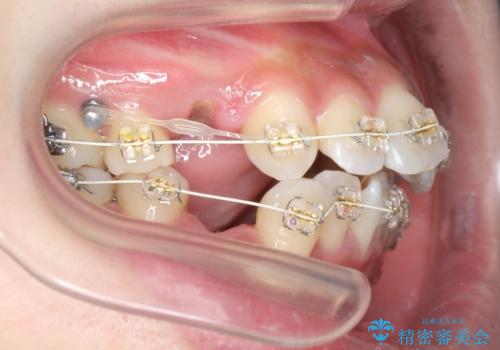

ガタつきと口元の改善 抜歯を伴うワイヤー矯正

- 唇の閉じづらさと、前歯のがたつきの改善を希望され来院されました。

抜歯を行わなくてもなんとか並べられる歯並びですが、唇の閉じづらさをしっかりと改善するため抜歯を伴うマルチブラケット矯正を行うこととしました。

前歯をしっかりと後方に引いたことで、唇は閉じやすくなり、仕上がりに満足いただくことができました。